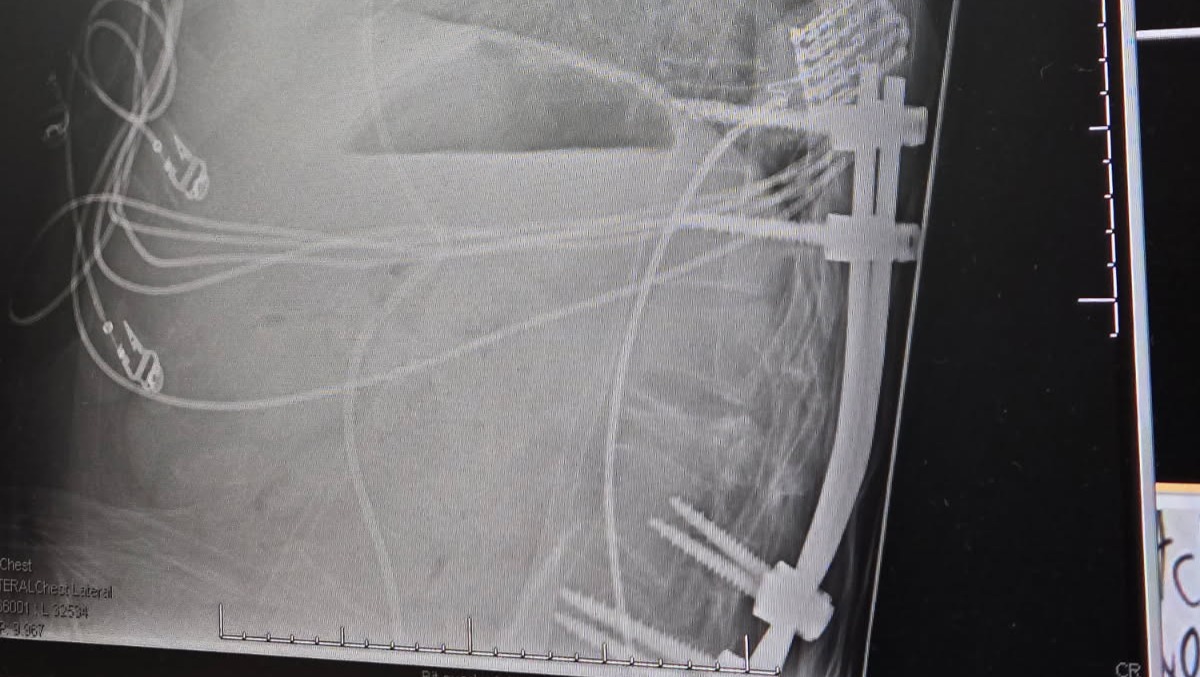

Following the spine surgery Dustin started having problems with his heart rate/blood pressure. The two main areas of concern currently are his liver and lungs. The masses in his lungs and pleural disease are growing quickly. The cancer is irritating the lining of his lungs causing fluid buildup which he has a drain in for currently. He has a metastatic mass in his chest pushing on his heart and the veins leading to his heart. Because of this pressure the heart cannot fill as much as it needs. His liver disease is stable however the mass is significant.

Ontop of everything Dustin has now contracted Covid. He is on an antiviral and antibiotics. The doctors are very concerned that in his current immunosuppressed state he may not be able to recover from covid and complications are likely. As Dustin's last chance at extra time he has chose to do a week of strong radiation on the mass in his chest. Typically they would wait until he recovers from covid to do radiation but Dustin can't wait. The tumor is very fast growing. Radiation started Thursday February 13th.